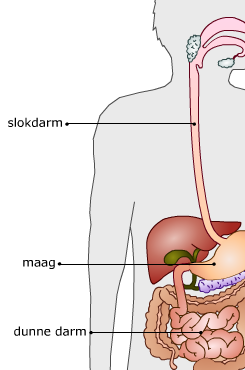

Verteringsstelsel

Een voorbeeld van een orgaanstelsel is het verteringsstelsel.

Een voorbeeld van een orgaanstelsel is het verteringsstelsel.

Drie organen die deel uit maken van het verteringsstelsel zijn de slokdarm, de maag en de dunne darm.

Slokdarm: Voert via peristaltische bewegingen voedsel van de mond naar de maag. |

Maag: Gespierd orgaan in de buikholte waarin het voedsel tijdelijk wordt opgeslagen en verteringssappen worden afgescheiden. |

Dunne darm: In de ongeveer 6 meter lange dunne darm vindt vertering plaats en worden voedingsstoffen door het bloed opgenomen. |